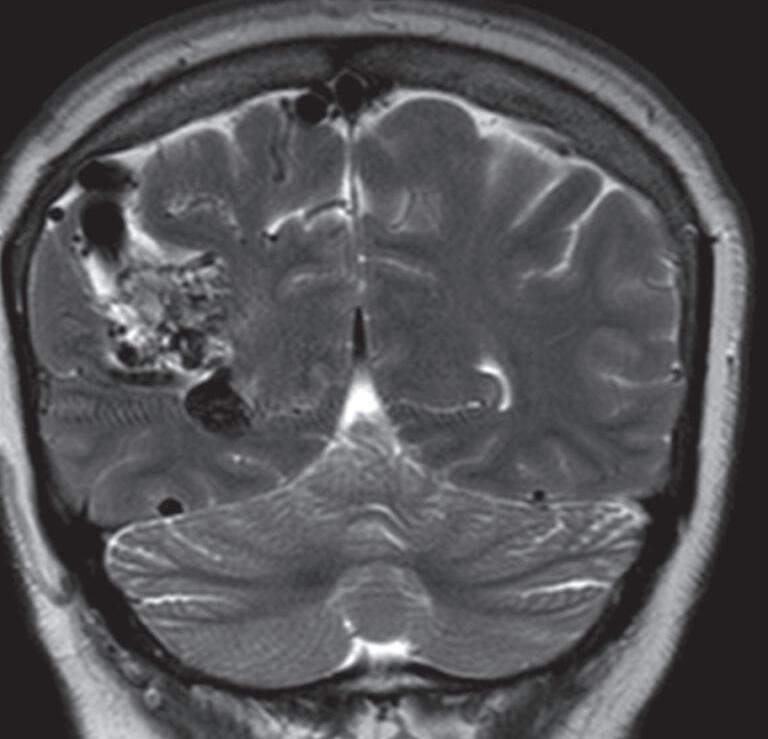

Fig. 1-8. (a-c) RNM T1 com contraste, cortes sagital (a), coronal (b) e axial (c) demonstrando MAV não rota com nidus localizado no lobo occipital à esquerda (setas longas). (d) Arteriografia digital cerebral com injeção de contraste via carótida direita (AP) mostrando a contribuição da carótida direita na irrigação da MAV contralateral. (e,f) Com injeção de contraste via carótida esquerda, em Perfil e AP respectivamente, observa-se nidus compacto nutrido por ramos da artéria cerebral média à esquerda e a veia de drenagem precoce se dirigindo para o seio sagital superior. Projeções em AP (g) e em perfil (h) demonstrando a contribuição do sistema vertebrobasilar por meio de ramos distais da artéria cerebral posterior à esquerda e drenagem para os seios sagital superior e sigmoide à esquerda (setas curtas).